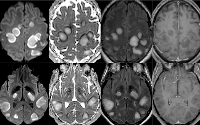

Multi-Institutional Study Looks at Brain MRI Findings in COVID-19

A new multi-institutional study published in Radiology identifies patterns in abnormal brain MRI findings in patients with COVID-19.The purpose of this current study was to describe the neuroimaging findings other than stroke in patients with severe COVID-19 and report the clinical and biological profile of these patients.